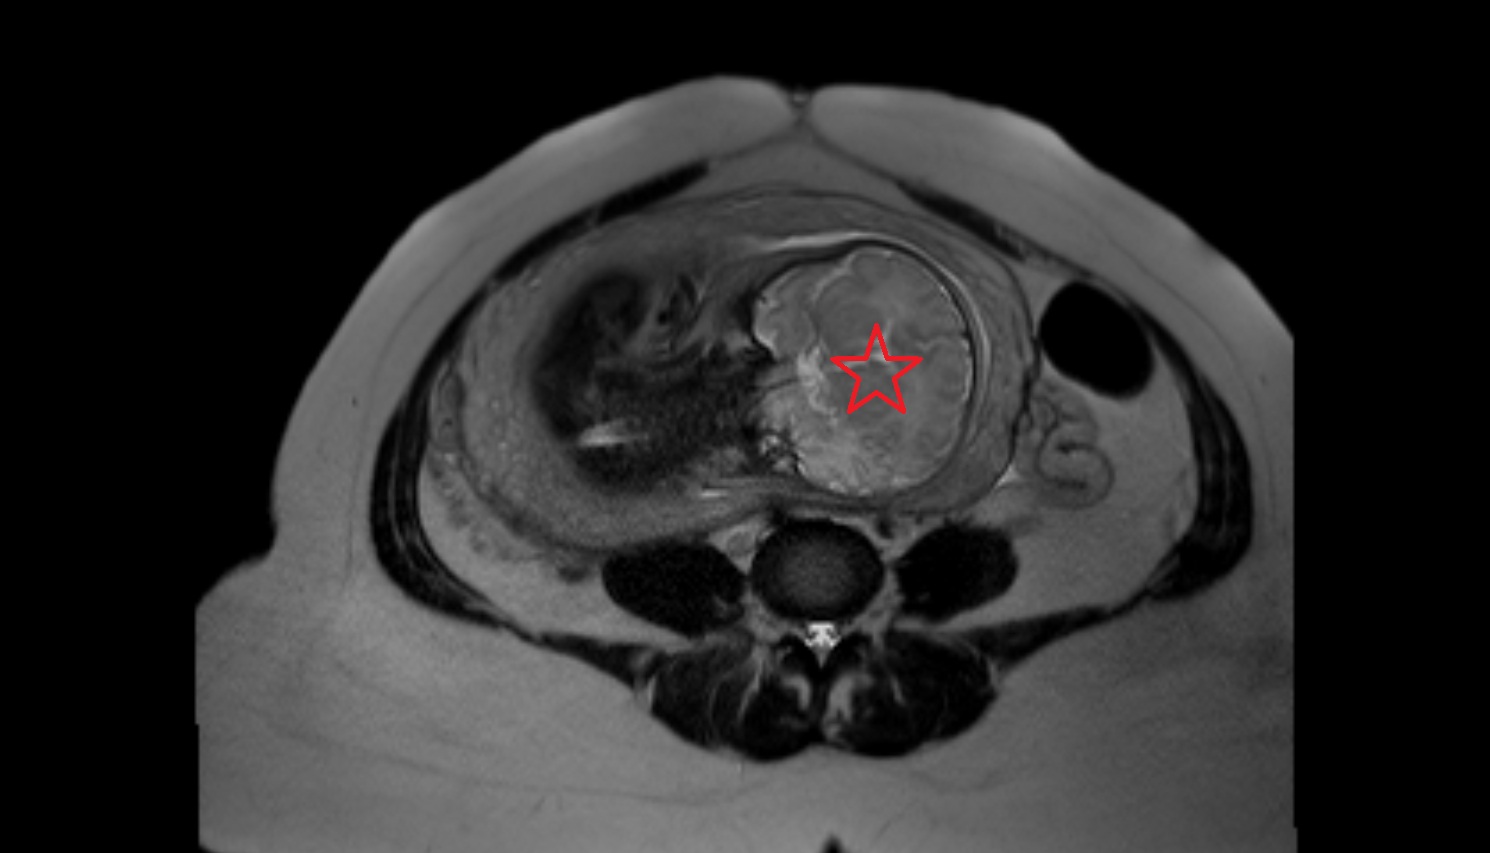

- Placenta

- Uterus (pregnancy)

- Amniotic fluid

- Fetal brain

- Fetal caudate nucleus

- Fetal thalamus

- Fetal cerebellum